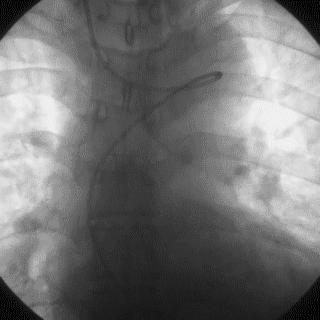

2014年,Patel T等首先采用球囊辅助通过技术(Balloon-assisted tracking,BAT),用于通过桡动脉途径中扭曲、细小节段(包括严重痉挛节段)(图1-2)。

图1

图2 BAT技术应用实例1。52岁女性患者冠脉严重痉挛(A),注射2次鸡尾酒后仍未缓解(B),采用BAT技术(C),顺利介导7F指引导管通过桡动脉严重痉挛节段(D)